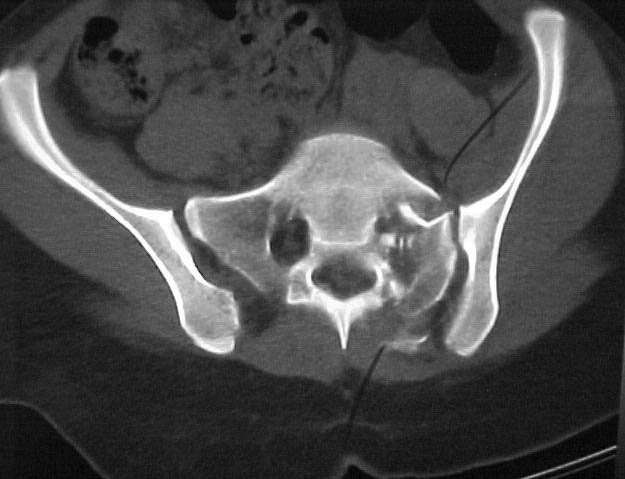

A 17 year old female involved in a car crash. Has a Type III lateral compression injury to her pelvic ring using the Young-Burgess classification. A windswept pelvis if you will. The images are included. There appears to be posterior displacement of the left hemipelvis as well.

My questions - should this be operated on? How to go about reducing the left side (i.e. correcting the posterior displacement as well as impaction) ? and How to fix it (iliosacral screws: posterior plate, etc.)? Thanks all!!